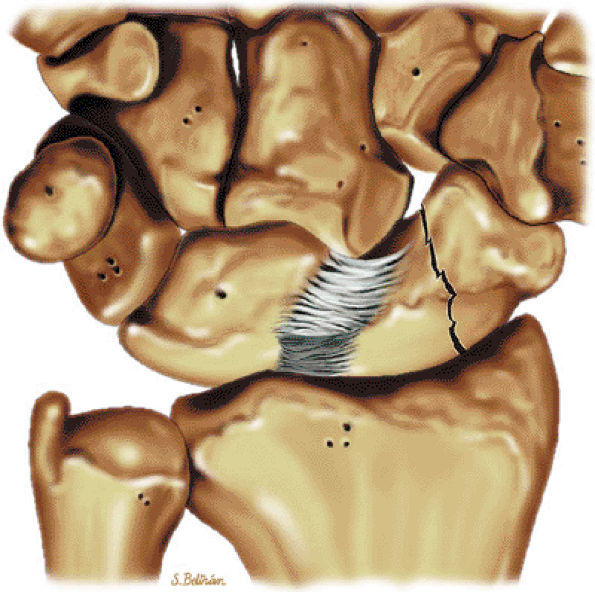

scaphoid, and also inserts on the center of the capitate.43 The radioscaphocapitate ligament forms a supporting sling at the waist of the scaphoid. As the fibers cross the proximal pole of the scaphoid, there is a fold of synovium that separates them from the bone.44 In this position, the ligament can be interposed between the fragments of a scaphoid fracture and contribute to nonunion. The radioscaphocapitate ligament, which has a striated appearance on volar coronal MR images, is located distal to the radiolunotriquetral ligament, which has a similar ulnodistal obliquity (Fig. 10.62). Sagittal images demonstrate the volar location of the radioscaphocapitate in cross-section relative to the waist of the scaphoid.